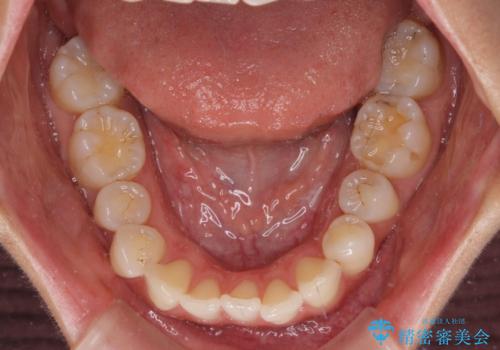

- 捻れた前歯が飛び出しており、口が閉じにくいとのことで来院された患者様です。

出っ歯というわけではないものの、前歯の捻転により口唇が押し出されている状態でした。

親知らずを抜去し、歯列全体を後方に移動させつつ、IPR(歯と歯の間を削る)でスペースを獲得し、インビザラインを用いて叢生を解消しながら前歯の突出を改善することとしました。